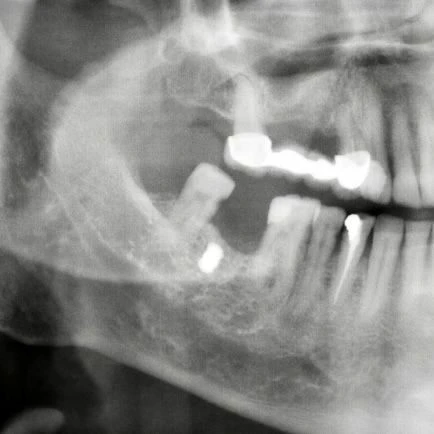

Erzincan’da yaşayan 63 yaşındaki Faik Akın, 15 yıl önce benzinli testereyle odun keserken testerenin zincirinin kopması sonucunda etrafa saçılan parçaların yüzüne isabet etmesi ile yaralandı. Hastaneye müracaat etmeyen Faik Akın’ın yüzüne gelen demir parçalardan biri damağında yıllarca kaldı. Diş tedavisi için hastaneye gelen Faik Akın’ı muayene eden Ağız ve Çene Cerrahı Dr. Öğretim Üyesi Yakup Gülnahar, hastanın röntgen filmine bakınca damağında bir nesne olduğunu belirledi.

Faik Akın'ın damağından kurşun büyüklüğünde demir parçası çıkarıldı.

Ameliyatı gerçekleştiren Dr. Yakup Gülnahar, “Hastanın muayenesinde rutin röntgen filmi istedik. Röntgenlerde hastanın yanağında bir cisim olduğunu anladım. Kendisine daha önce implant yaptırıp yaptırmadığını sordum. Kendisi implant yaptırmadığını söyledi. Bu sefer hastanın yanağında ne olabilir diye düşünürken hastanın 15 yıl önce benzinli odun testeresi ile çalışırken testerenin zincirinin koptuğunu ve etrafa saçılan parçalardan yanağına isabet ettiğini öğrendik. Hastamızı ameliyata aldık ve yanağındaki demir parçayı çıkardık. Hastamız da şu an gayet iyi bir durumda” şeklinde konuştu.